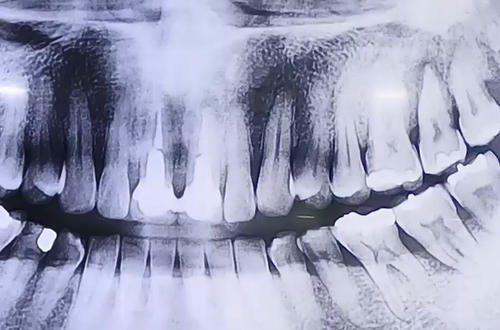

AFTER

왼쪽 위 어금니 두 개를 발치하게 되었는데,

하나는 잇몸 뼈의 상태가 괜찮아 즉시 식립으로 진행하였고

하나는 잇몸 뼈가 단단하지 않아서 염증을 깨끗이 치료하고 뼈이식을 한 뒤

기다렸다가 진행하는 지연 식립 임플란트로 진행한 사례입니다.